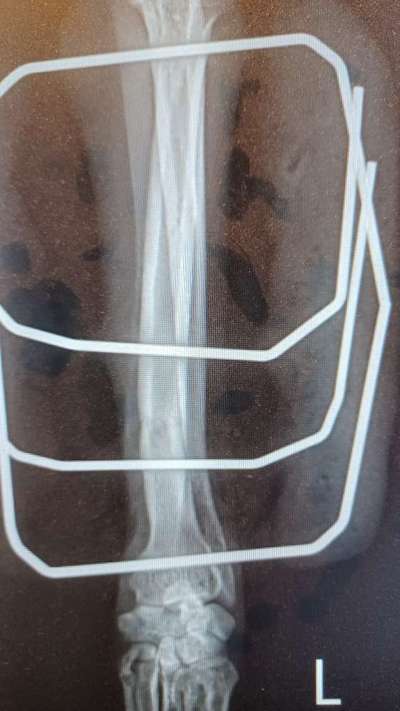

Lucy hat sich das Vorderbein gebrochen. Ein unkomplizierter Bruch der Speiche. Gestern wurde bei ihr ein Fixateur extern montiert. In 2-3 Tagen kann sie nach Hause. Der Fixateur soll etwa 6 Wochen dran bleiben. EDIT: Ich habe 2 Fotos und Röntgenbilder ergänzt, damit man eine Vorstellung hat, wie so etwas aussehen kann. Wenn wir sie abholen, bekommen wir natürlich noch genauere Infos vom Arzt, was wir beachten müssen. Trotzdem fragen wir uns jetzt schon, wie wir damit im Alltag umgehen sollen. Hat jemand Erfahrungen mit einem Fixateur extern? Was ging damit gut, was ging nicht? Was hat Euch überrascht? Wir sind für jegliche Informationen dankbar. EDIT: Hier noch mal die Eckdaten: 29.07.2023 Lucy bricht sich das Vorderbein 30.07.2023 In der Tierklinik wird das Bein mit einem externen Fixateur stabilisiert 02.08.2023 Lucy wird aus der Klinik entlassen Bis zu 10 Minuten am Stück gehen, nicht Springen, Toben, Rennen Ab 18.09.2023 ist bis zu 30 Minuten am Stück gehen erlaubt 2x Entzündung an den Pinnen des Fixateurs 3x Kontrollröntgen 25.10.2023 Der Fixateur wird in der Klinik entfernt Das Bein wird durch einen Verband geschützt und stabilisiert, der alle 2 - 3 Tage beim Tierarzt gewechselt wird Bis zu 10 Minuten am Stück gehen, nicht Springen, Toben, Rennen 02.11.2023 Der Verband ist ab 07.11.2023 kein Kragen mehr nötig

Hier sind die Röntgenbilder vom 18.9.23

Man sieht, dass sich da schon viel getan hat, und dass der Knochen gerade zusammen wächst. Aber es ist auch deutlich zu sehen, dass noch Substanz fehlt.

Wir hoffen nun auf das Kontrollröntgen am 16.10.